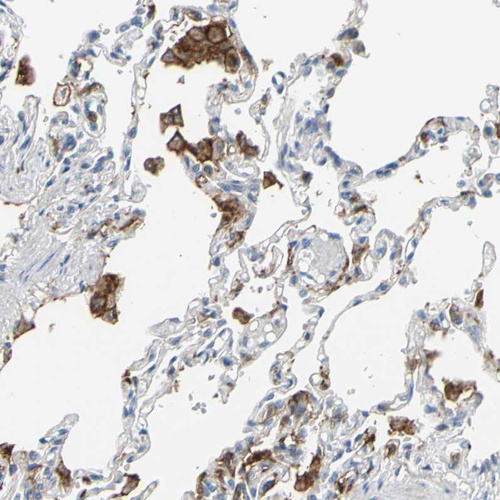

Immunohistochemical staining of human lung shows strong cytoplasmic/membranous positivity in macrophages.